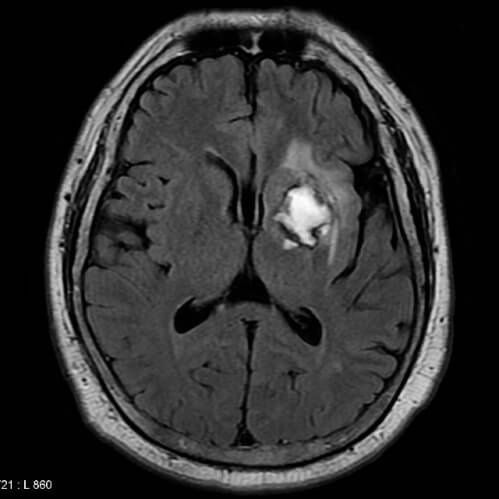

Magnetska rezonancija mozga pacijenta koji imao moždani udar. Zbog nakupljanja kolesterola krvna žila je pukla i krvari u mozak. Krv se nakuplja i komprimira okolno

moždano tkivo.